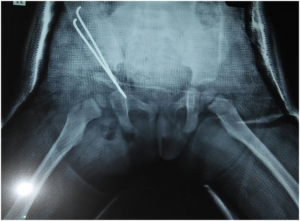

Parents came to me with their 1.5 yr old kid with limping (right side). After medical investigation, I found her right hip dislocated. She also had problems of ligamentous laxity.

In medical practice, there is no standard guideline to deal with congenital dislocation of hip with ligamentous laxity. So, I counselled parents for all possible options and went for major operation.

I asked them to come for regular follow ups. But they were lost to follow up. After 1 year, they came again with the following…

congenital-hip-dislocation-xray